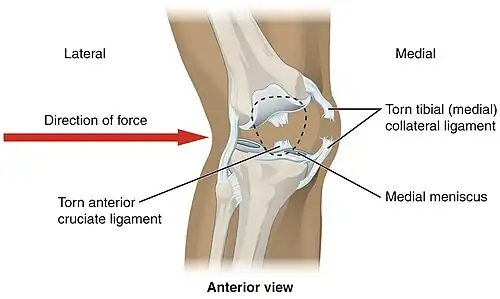

Common injuries due to physical activity

In sports that place great pressure on the knees, especially with twisting forces, it is common to tear one or more ligaments or cartilages. Some of the most common knee injuries are those to the medial side: medial knee injuries.[32]

Anterior cruciate ligament injury

The anterior cruciate ligament is the most commonly injured ligament of the knee. The injury is common during sports. Twisting of the knee is a common cause of over-stretching or tearing the ACL. When the ACL is injured a popping sound may be heard, and the leg may suddenly give out. Besides swelling and pain, walking may be painful and the knee will feel unstable. Minor tears of the anterior cruciate ligament may heal over time, but a torn ACL requires surgery. After surgery, recovery is prolonged and low impact exercises are recommended to strengthen the joint.[33]